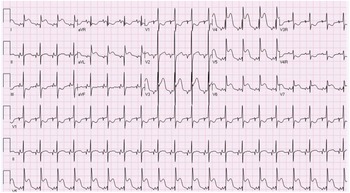

A term male infant was diagnosed postnatally at day 2 after being noted to have tachypnoea which prompted a cardiology workup and was noted to have hypoplastic left heart syndrome with severe mitral and aortic valve stenosis. At 1 week, he underwent Norwood procedure with Sano shunt placement. The Norwood was done with incising down the ascending aorta with side-to-side anastomosis with continuous monofilament sutures with knots on the outside. He had uncomplicated post-operative course and was extubated on post-operative day #5. His initial post-op echo showed unrestrictive atrial septal defect, mild tricuspid regurgitation, patent aortic arch, and Sano shunt with patent Damus–Kaye–Stansel anastomosis with no thrombus noted (Fig 1). On post-operative day #9, he was noted to have sudden onset clinical change after a routine chest physiotherapy and was noted to have sudden onset of bradycardia and hypotension, elevated ST segments with low cerebral and somatic Near Infra-Red Spectroscopy, and elevated blood lactate. A 15 Lead electrocardiogram showed ST elevation (Fig 2). His native aortic root measured around 5 mm and the ascending aorta was 4 mm. The sinotubular junction of the native aortic root measured around 4 mm. An echocardiogram showed a large thrombus (around 5 × 3.5 mm) in his aortic root occluding blood flow into the left main coronary artery (Fig 3a). His labs showed elevated troponins with an initial value of around 14 ng/ml (reference range 0–0.39 ng/ml) which peaked to around 83 ng/ml within 24 hours, with resolution over a week. The patient was intubated, started on low dose epinephrine, and sedated and paralyzed with improved haemodynamics. Haematology was consulted and the patient was started on low dose tissue plasminogen activator at around 0.06 mg/kg/hour, which was titrated to around 0.08 mg/kg/hour based on clot size. Repeat echocardiogram imaging over the next few days revealed decreasing clot size and eventual resolution of thrombus with adequate perfusion of coronary arteries after 72 hours of thrombolysis treatment (Fig 3b).

Figure 2. 12 Lead EKG showing evidence of ST elevation in Lead I, AVL, and V4-V6.

In our patient, clinical presentation was manifested as ST segment elevation on EKG reflecting ischaemia with elevated troponins. Other previous cases reported in the literature Reference Janssen, Ohmstede, Liske, Parra, Drinkwater and Ann1–Reference Brennan, Rodefeld, Tacy, Reddy and Hanley4,Reference Graham, Shakir and Bradley6,Reference Kosaka, Sakamoto, Takigiku, Yasukochi and Harada7 showed patients in age range of 7 days to 4 years who presented with EKG changes like ST depression, T wave inversion, non-sustained ventricular tachycardia, and complete heart block. Some patients had symptoms of chest pain, and most patients were noted to have elevated biomarkers such as troponin. Some patients with native aortic root thrombus did show evidence of ventricular dysfunction. Most patients were diagnosed with transthoracic echocardiography with one patient diagnosed with cardiac catheterisation. Routine evaluation of the aortic root in all patients who present with new sudden onset RV dysfunction should be done to screen for a possible thrombus in the native aortic root with assessment of coronary flow on echocardiogram. Cardiac catheterisation or advanced imaging should be done in cases with clinical evidence of ischaemia but poor echocardiographic windows or concern for thrombus in coronary arterial system which cannot be assessed with transthoracic echocardiogram.